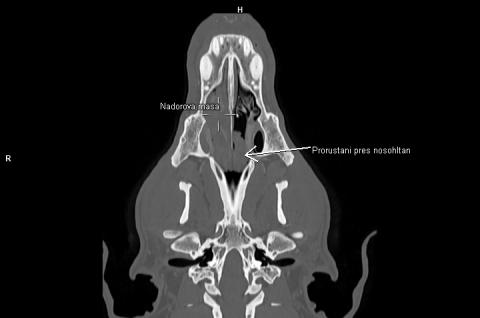

CT diagnostika nádorů hlavy a krku